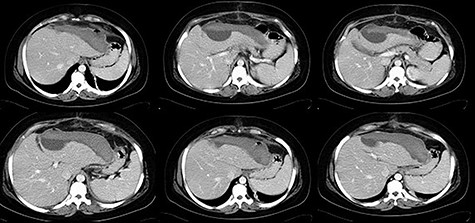

Thirty-one-year-old pregnant woman, primigravida, with history of obesity, admitted at 35 weeks of gestation due to pain in the right abdomen with 2 weeks of evolution. On admission: hemodynamically stable with tenderness on the right quadrants of the abdomen. The initial blood work only revealed thrombocytopenia (120 × 103/μl) and impaired hepatic function (AST 65 U/L, ALT 88 U/L). The patient was kept on observation, with aggravation of symptoms. Blood work showed anemia (6.9 g/dl), thrombocytopenia (113 × 103/μl) and impaired hepatic function (AST 363 U/L, ALT 399 U/L, LDH 505 U/L). The patient underwent an emergency c-section, during which an extensive hemoperitoneum was observed. It was then converted to median laparotomy in which was observed hepatic rupture of segments V, VI and VII; packing was performed and the abdomen closed. A second-look laparotomy was performed 48 hours later. Two new subcapsular hematomas were found in the left lobe, but without active hemorrhage, which led to the removal of the packing (Figs 3–5).

The patient recovered without complications and was discharged on the 13th postoperative day (Fig. 6).